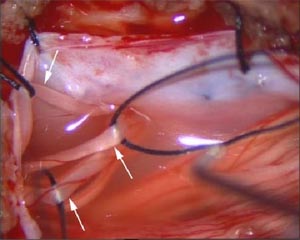

脊神经后根分成几小束(↑所示)

神经阈值测定仪电刺激神经后根小束(↑所示)

切除一小段阈值最小的神经后根小束(↑所示)